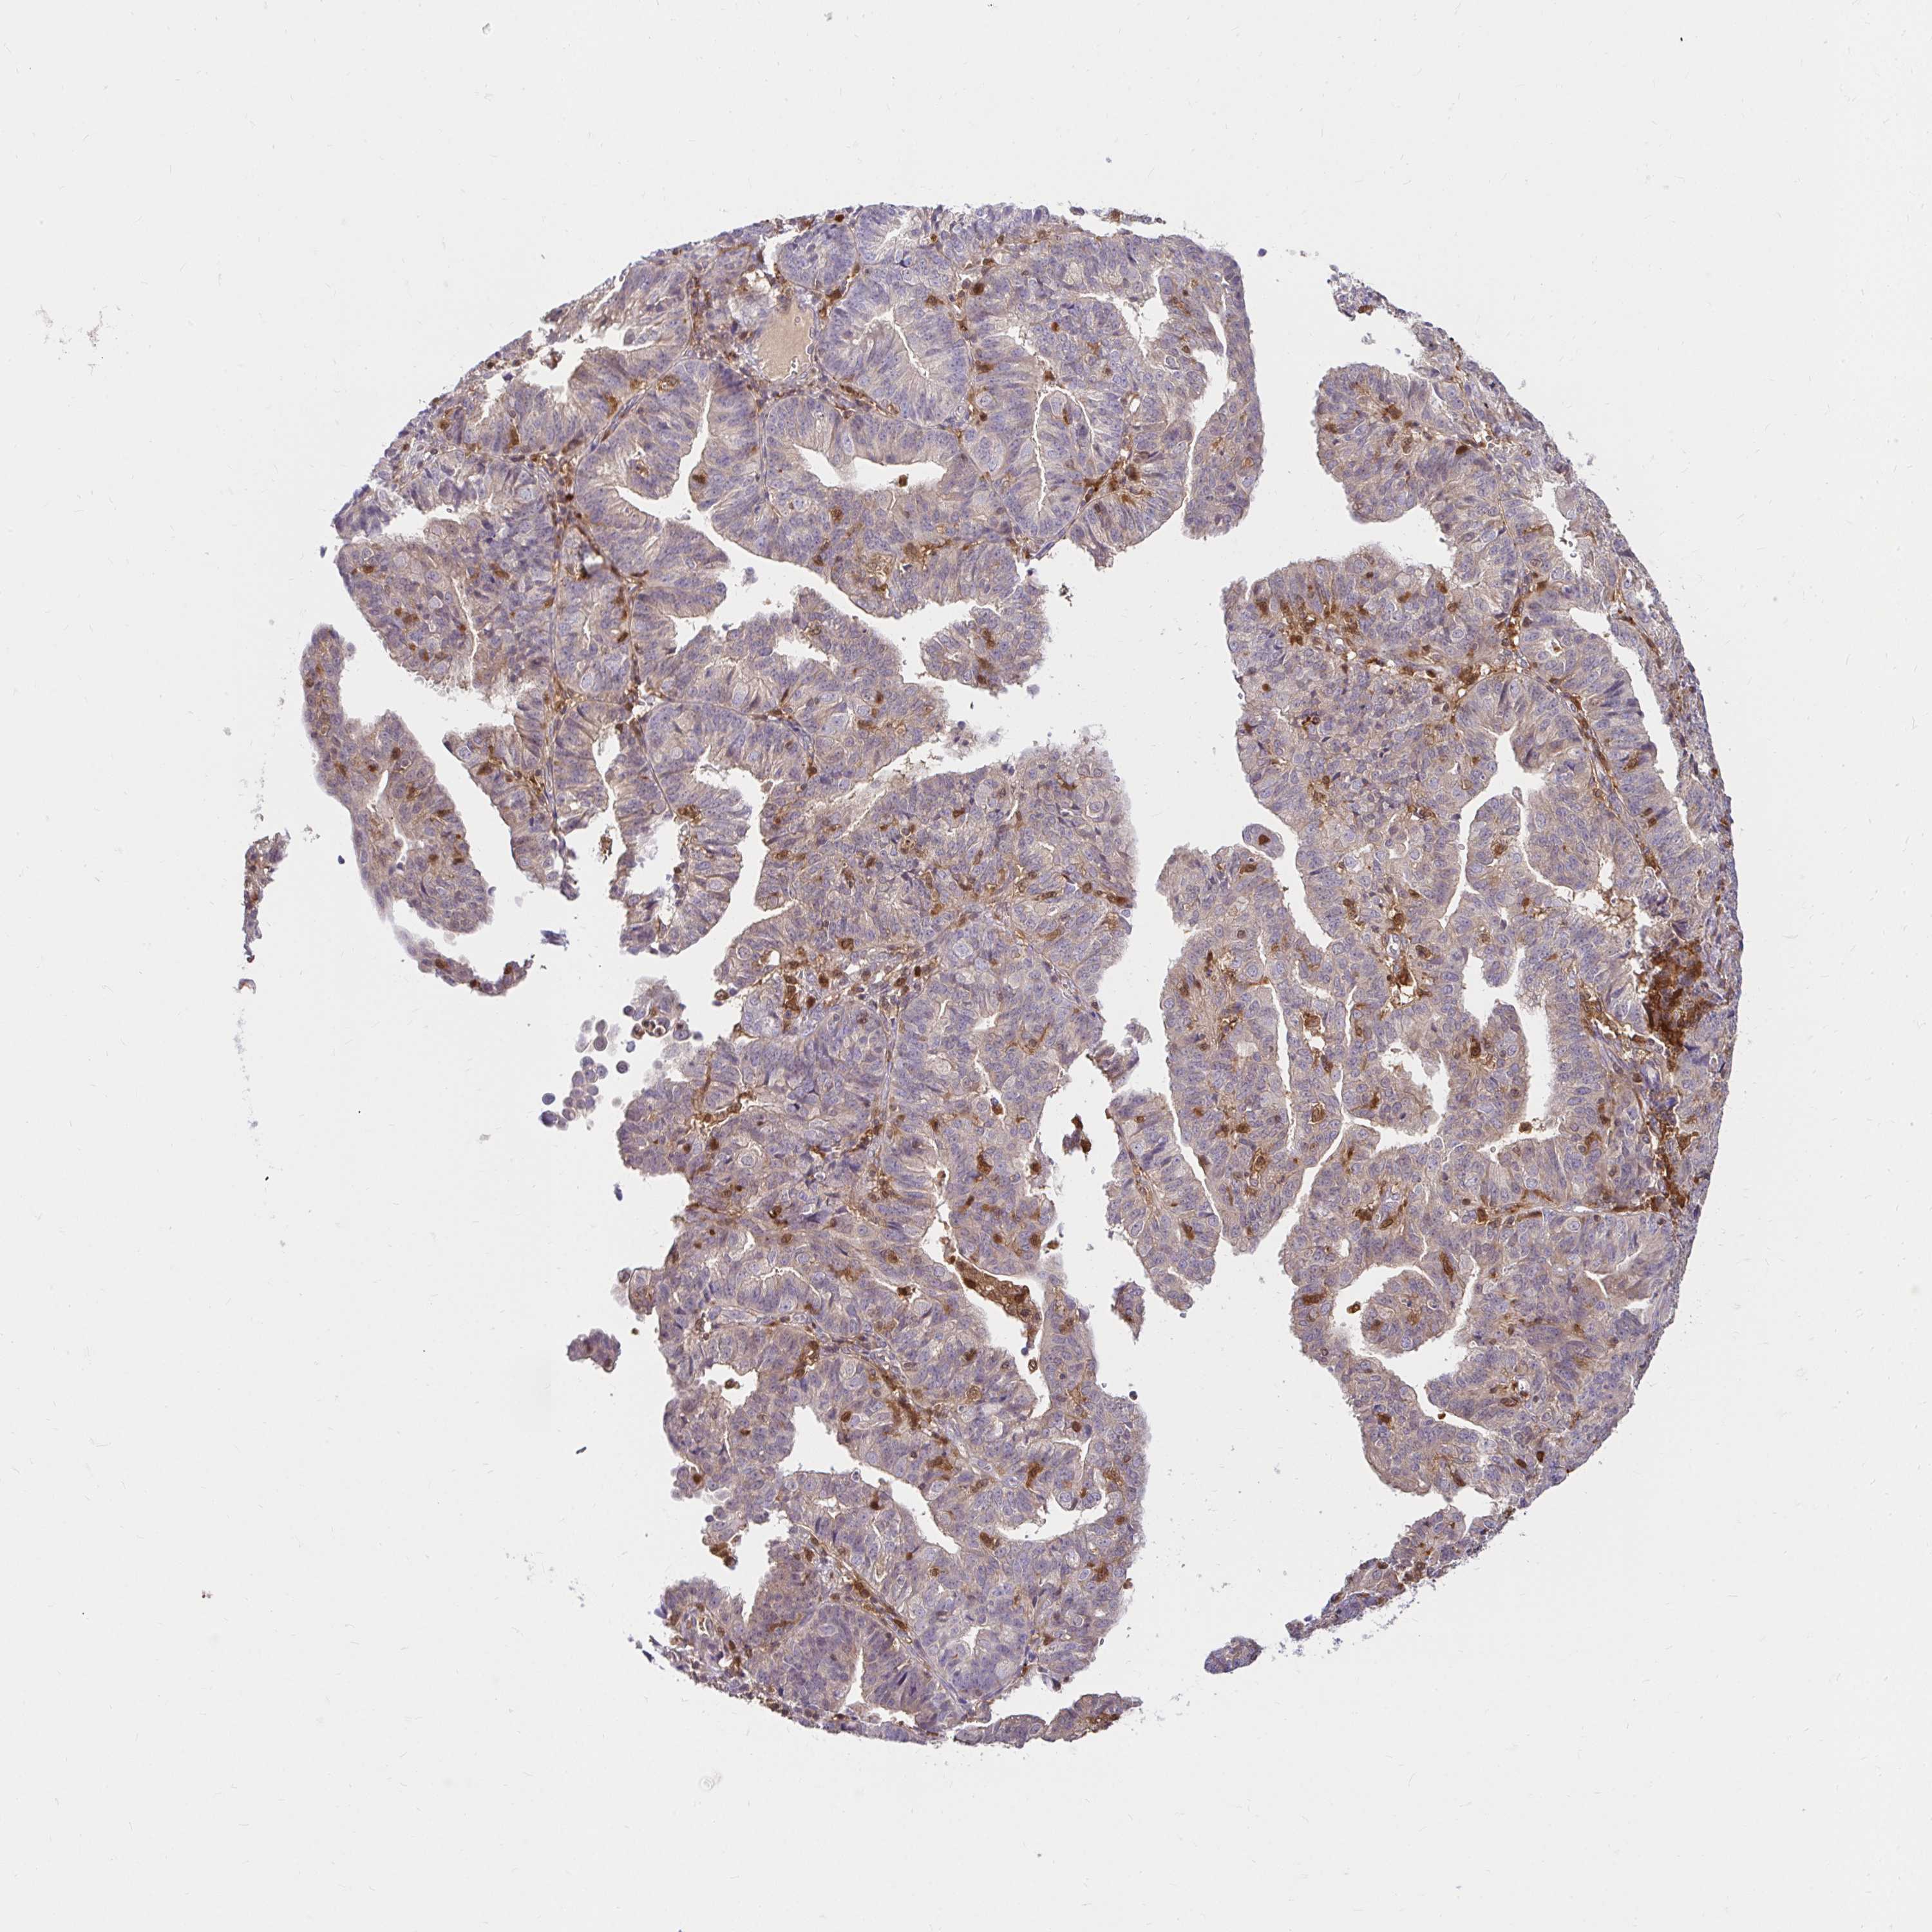

ENDOMETRIAL CANCER - Protein expressioni

A mouse-over function shows sample information and annotation data. Click on an image to view it in a full screen mode. Samples can be filtered based on level of antibody staining by selecting one or several of the following categories: high, medium, low and not detected. The assay and annotation is described here.

Note that samples used for immunohistochemistry by the Human Protein Atlas do not correspond to samples in the TCGA dataset.

Antibody stainingi

Antibody staining in the annotated cell types in the current human tissue is reported as not detected, low, medium, or high, based on conventional immunohistochemistry profiling in selected tissues. This score is based on the combination of the staining intensity and fraction of stained cells.

Each image is clickable and will lead to virtual microscopy that enables deeper exploration of all samples and also displays staining intensity scores, fraction scores and subcellular localization as well as patient and tissue information for each sample.

Antibody HPA049074

Antibody HPA054496

Antibody CAB006853

Antibody CAB015948

Staining

High

Medium

Low

Not detected

Intensity

Strong

Moderate

Weak

Negative

Quantity

>75%

75%-25%

<25%

None

Location

Nuclear

Cytoplasmic/membranous

Cytoplasmic/membranous,nuclear

Adenocarcinoma, NOS

Carcinoma, NOS

Adenocarcinoma, metastatic, NOS

Neoplasm, malignant, NOS